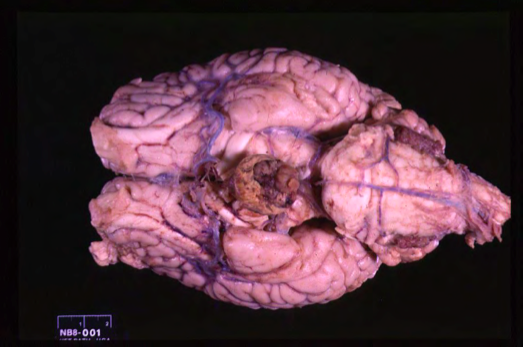

Corticotroph adenomas comprised of cells which can secrete

Corticotroph adenomas comprised of cells which can secrete ACTH.

Most of the Cushings cases are dependent on what?

In dogs, ~85% of Cushing’s cases are “pituitary dependent” (secondary), ~15% “adrenal dependent” (primary).

Pituitary adenomas in dogs

In dogs, the majority of pituitary adenomas are active and from the pars distalis>>intermedia.